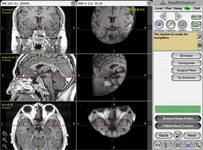

Bu durumlar, hastaların yaşam kalitesini etkileyebilir ve cerrahi müdahale gerektirebilir. Ameliyat Öncesi DeğerlendirmeHipofiz ameliyatı öncesinde, doktorlar hastanın genel sağlık durumunu değerlendirmek için aşağıdaki adımları izler:

Bu değerlendirmeler, cerrahinin gerekliliğini ve ameliyatın risklerini belirlemek için önemlidir. Ameliyat SüreciHipofiz ameliyatı genellikle genel anestezi altında yapılır. Ameliyat süreci şu aşamalardan oluşur: